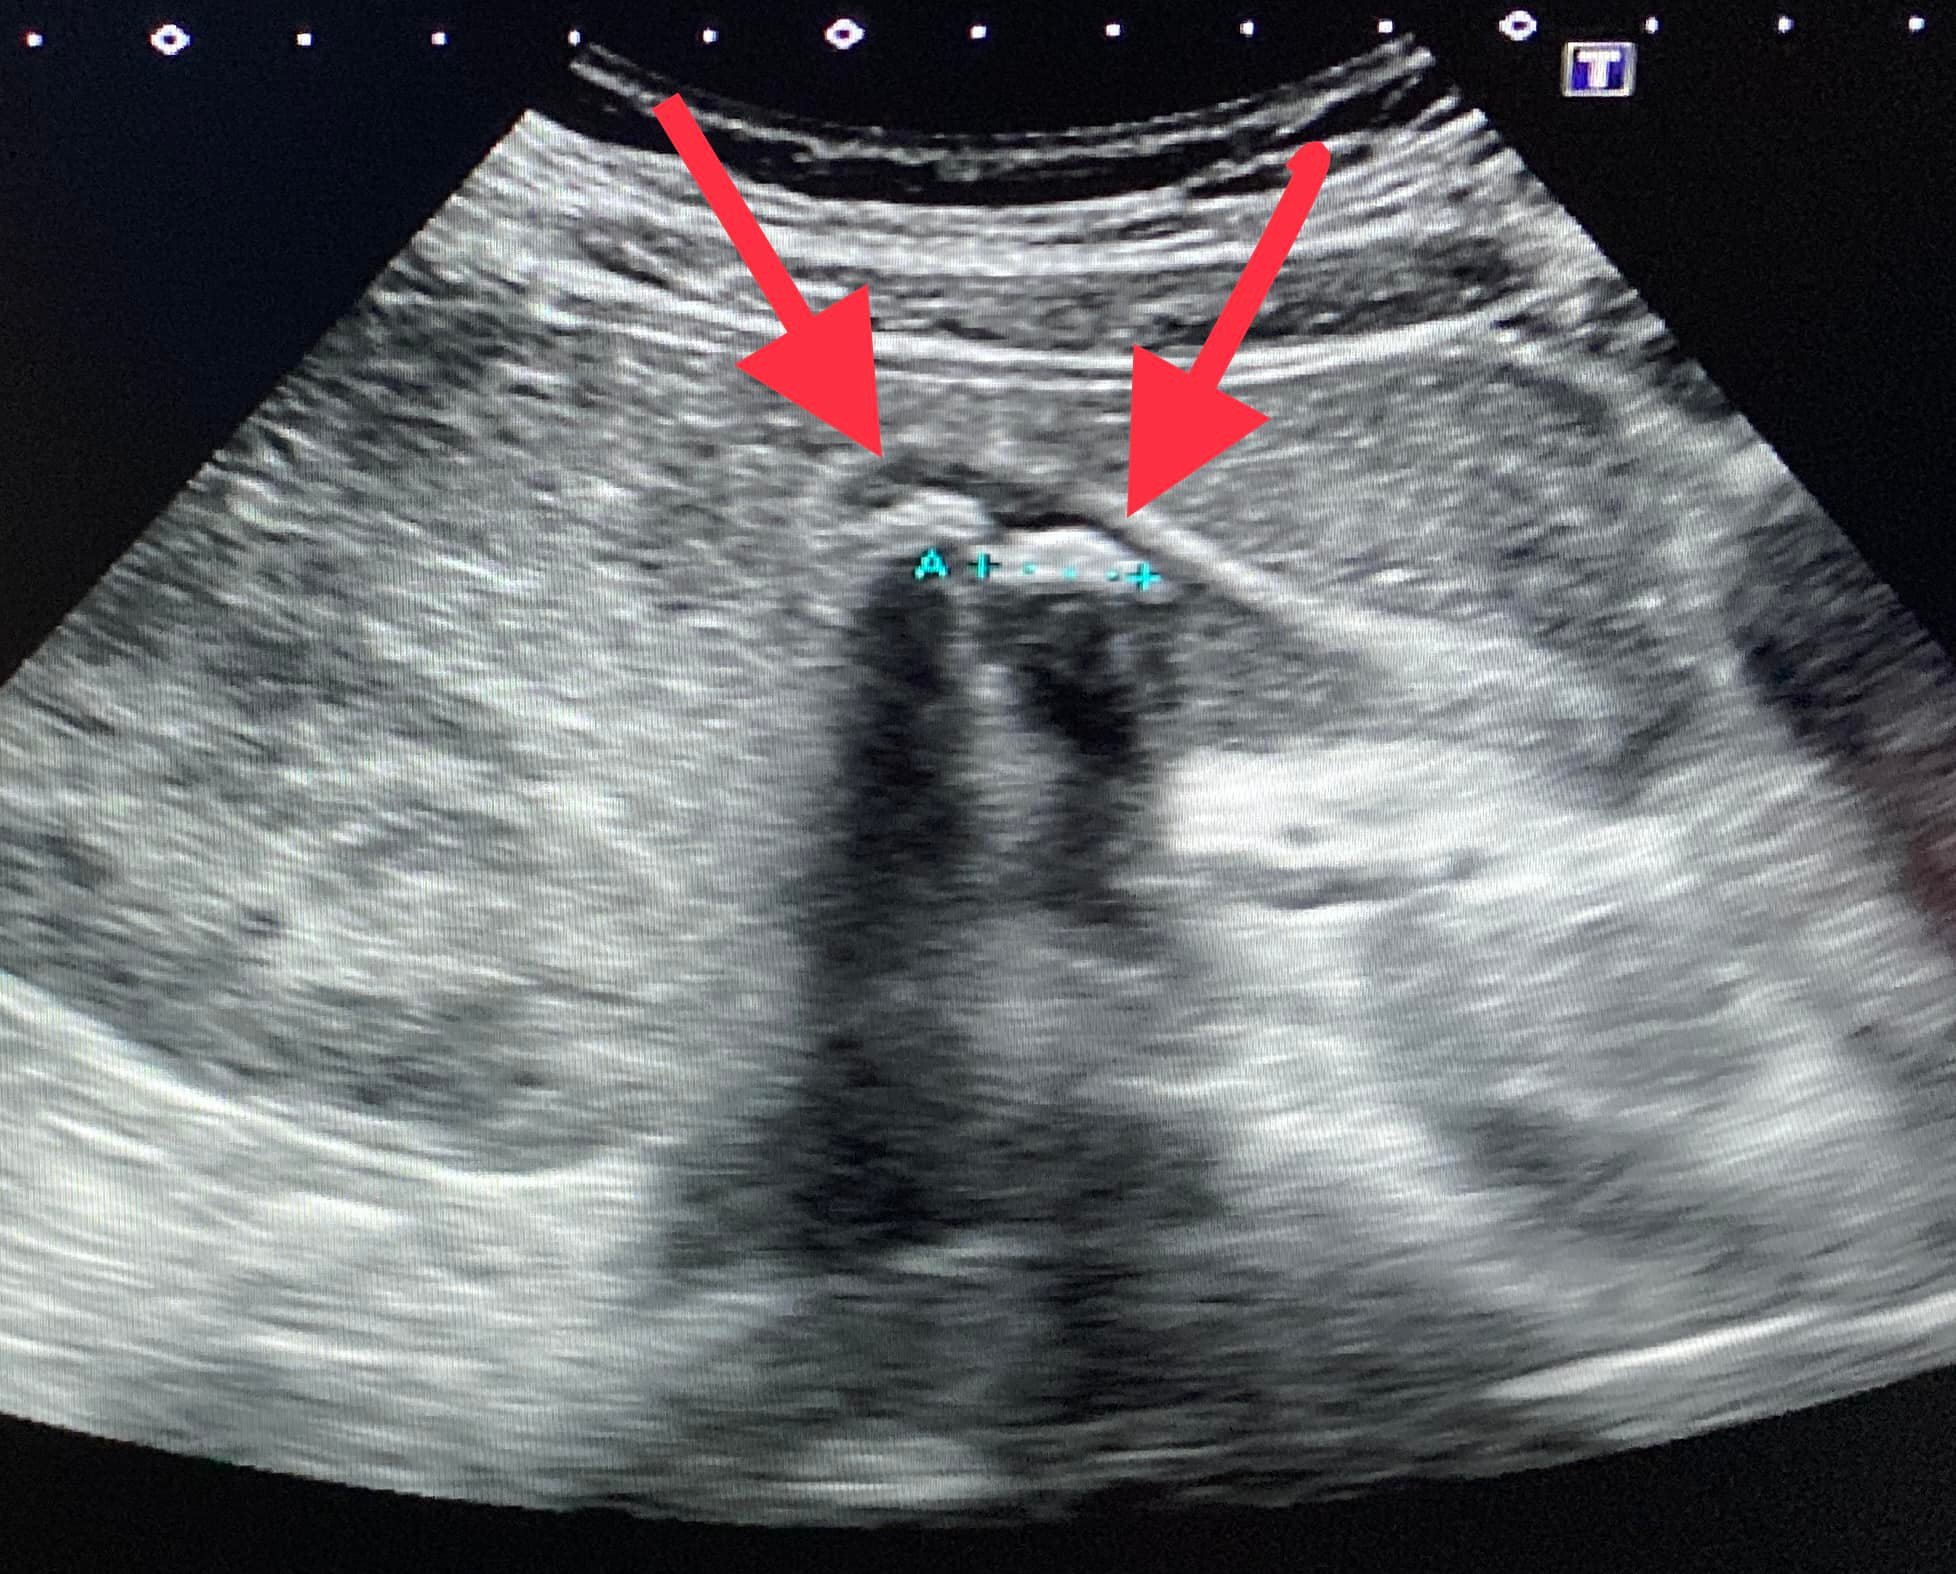

聽聞這些症狀,錢政弘推斷,高中生的不適恐怕是膽結石所導致,雖然十二指腸潰瘍也會在半夜疼痛,但痛感不會如此劇烈。後來高中生進行超音波檢查,錢政弘看見他的膽囊裡已經沒有正常的膽汁,全被膽泥取代,且至少有五顆1.2公分以上的結石在膽囊中漂浮,這讓見多識廣的錢政弘感到驚訝,「我是常見到膽結石的病患,不過這位年輕人才17歲耶!他的結石這麼多,應該前幾年就有了。」

▼17歲高中生膽囊中漂著至少五顆結石。(圖/錢政弘胃腸肝膽科醫師臉書粉專)